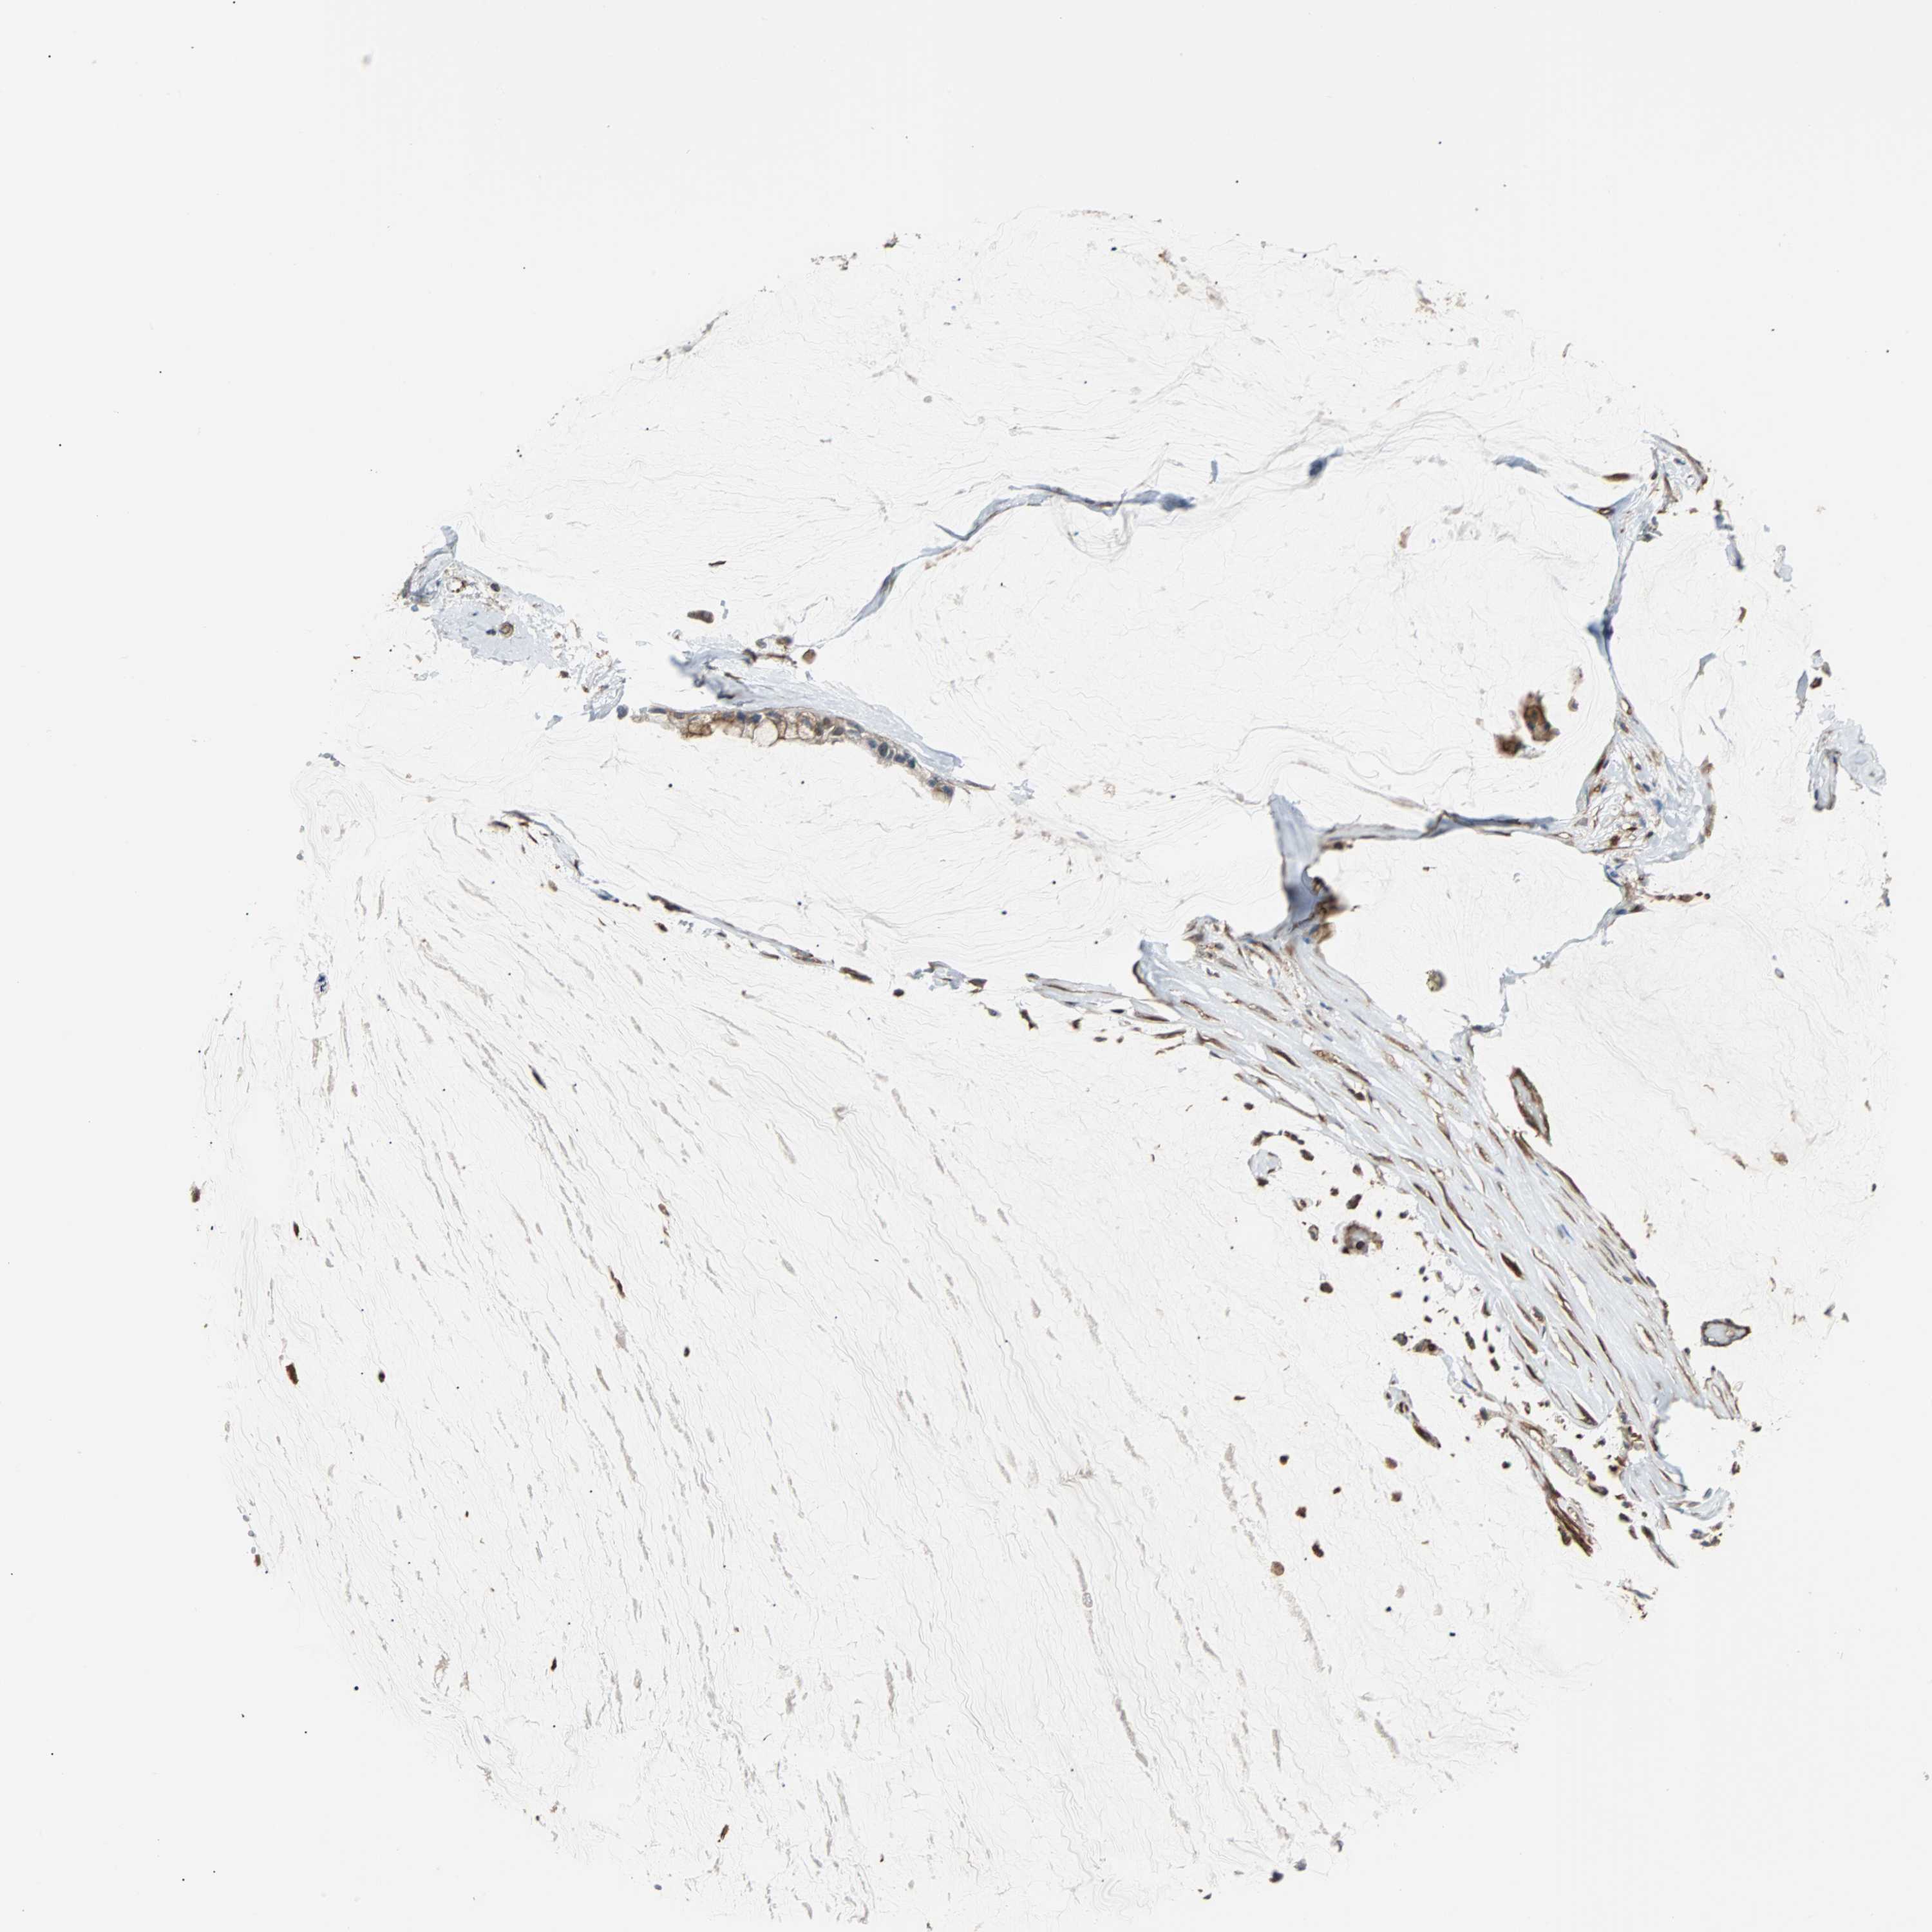

OVARIAN CANCER - Protein expressioni

A mouse-over function shows sample information and annotation data. Click on an image to view it in a full screen mode. Samples can be filtered based on level of antibody staining by selecting one or several of the following categories: high, medium, low and not detected. The assay and annotation is described here.

Note that samples used for immunohistochemistry by the Human Protein Atlas do not correspond to samples in the TCGA dataset.

Antibody stainingi

Antibody staining in the annotated cell types in the current human tissue is reported as not detected, low, medium, or high, based on conventional immunohistochemistry profiling in selected tissues. This score is based on the combination of the staining intensity and fraction of stained cells.

Each image is clickable and will lead to virtual microscopy that enables deeper exploration of all samples and also displays staining intensity scores, fraction scores and subcellular localization as well as patient and tissue information for each sample.

Antibody CAB004264

Antibody CAB005030

Staining

High

Medium

Low

Not detected

Intensity

Strong

Moderate

Weak

Negative

Quantity

>75%

75%-25%

<25%

None

Location

Nuclear

Cytoplasmic/membranous

Cytoplasmic/membranous,nuclear

Cystadenocarcinoma, serous, NOS

Carcinoma, endometroid

Carcinoma, NOS

Cystadenocarcinoma, mucinous, NOS